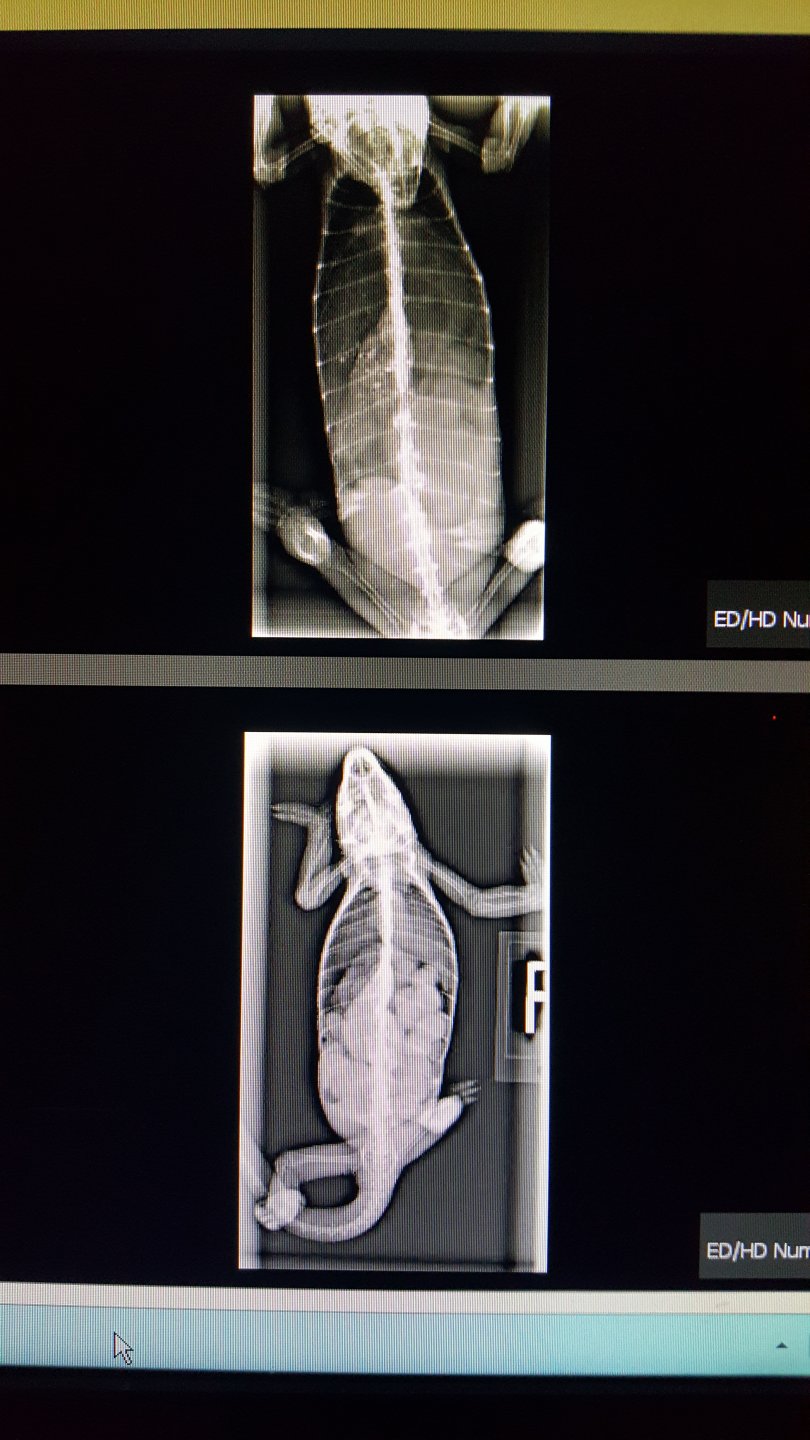

For reference and comparison, he took xrays to see what changes had occurred. Pictures below. He said that there has not been much change. There has not been any shell/calcification made to the eggs/follicles... her belly is still soft.